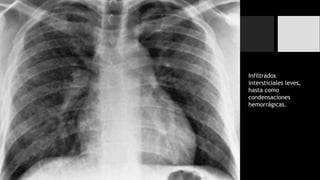

Neumonía Intersticial

• Neumonías víricas y micóticas.

• Tienden a afectar las paredes de las vías respiratorias así como de los tabiques alveolares.

• Dan lugar a un patrón reticular fino en los pulmones en rx.

• Comúnmente se diseminan a todo el pulmón con aspecto parcheado o confluyente.

Neumonías Virales

Infiltrados

intersticiales leves,

hasta como

condensaciones

hemorrágicas.

Neumonía Intersticial • Neumoníasvíricas y micóticas. • Tienden a afectar las paredes de las vías respiratorias así como de los tabiques alveolares. • Dan lugar a un patrón reticular fino en los pulmones en rx. • Comúnmente se diseminan a todo el pulmón con aspecto parcheado o confluyente.